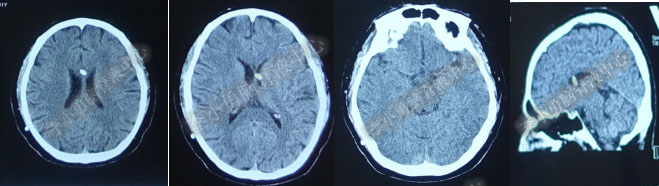

第4次出院后11天即2018年4月15日(分流术后284天,第2次的软性内镜术后179天),因引流管堵塞第5次住入该院,引流管内白色絮状物增多,引流管被堵塞。入院当天复查头部CT(图-10)显示脑室系统仍扩张。

图-10:2018年4月15日头部CT

第5次入院第2天即2018年4月17日,脑室腹壁外引流管堵塞,意识恶化,复查头部CT(图-11)示全脑室系统又较前扩大。当天急诊行左侧脑室穿刺外引流术。脑脊液化验外观黄色浑浊,并且送培养,结果是无菌生长。

图-11:2018年4月17日头部CT脑室扩张又加重

第5次入院第3天即2018年4月18日术后复查头部CT(图-12)显示脑室系统扩张较前好转。

图-12:2018年4月18日头部CT